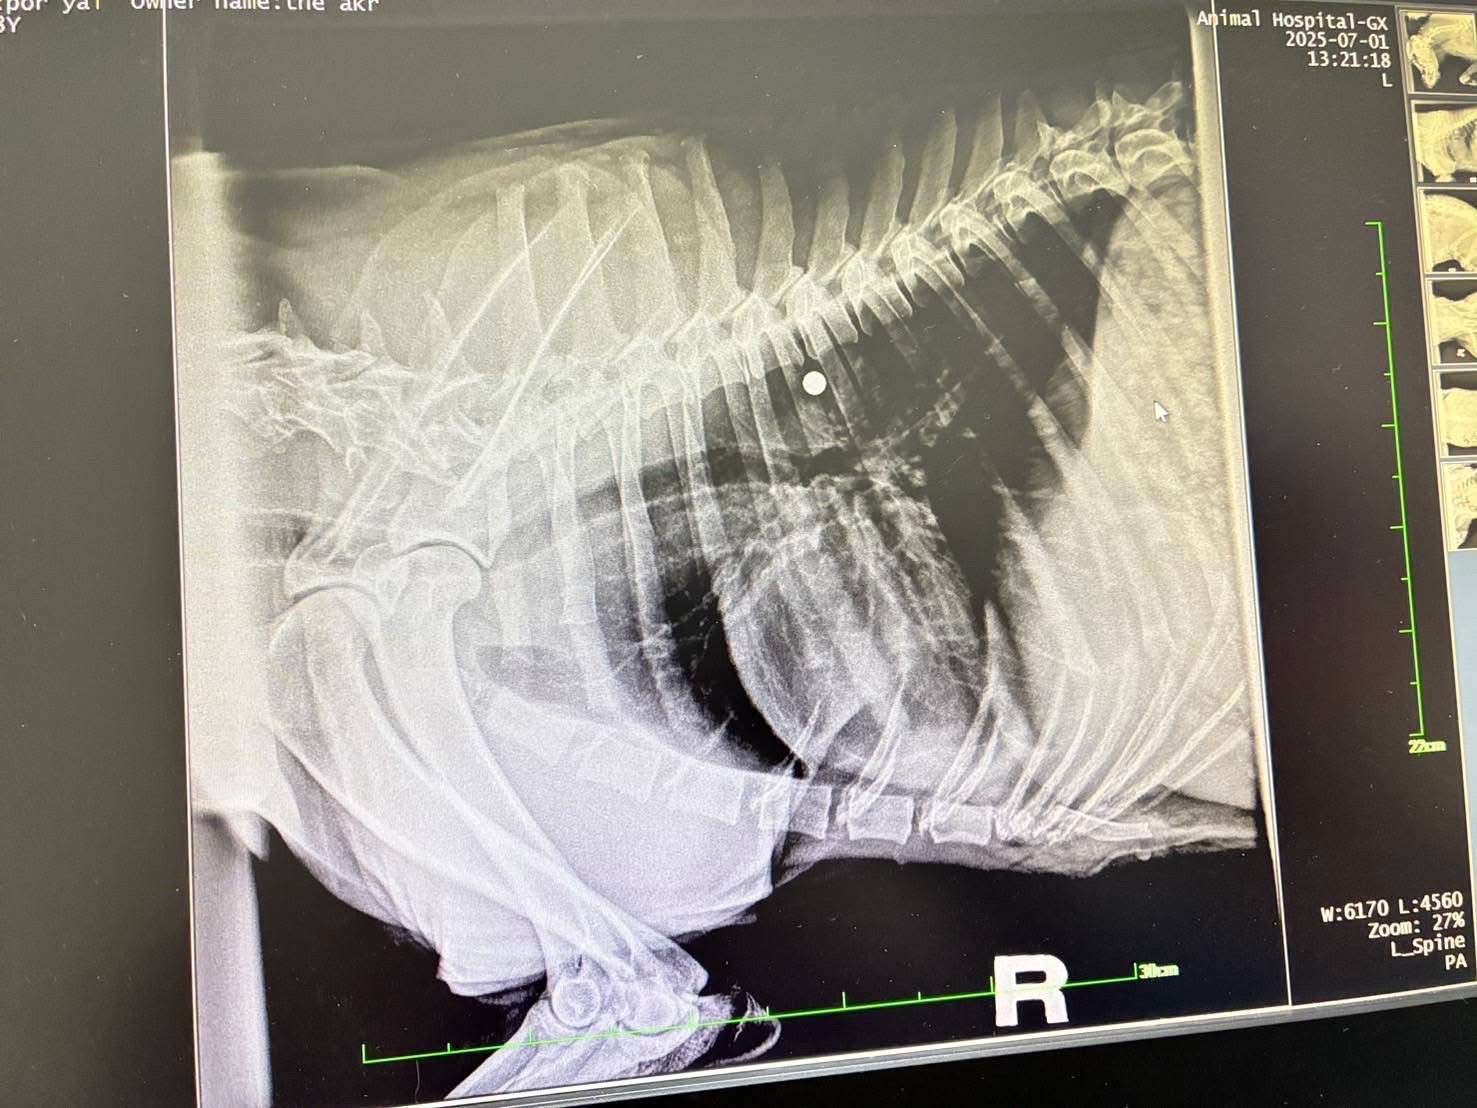

เมื่อวันที่ 1 กรกฎาคม 2568 พระครูสังฆรักษ์วีรวัฒน์ วีรวฑฺฒโน (พระครูอ๊อด) วัดเจดีย์หลวงวรวิหาร จังหวัดเชียงใหม่ เปิดเผยว่า ได้รับรายงานจากมูลนิธิ ดิอาร์ค ในพระราชูปถัมภ์ ซึ่งรับดูแลสุนัขพันธุ์ร็อตไวเลอร์จำนวน 4 ตัวที่ถูกนำไปทิ้งไว้กลางป่าในสภาพหิวโซและมีอาการบาดเจ็บหลายแห่ง โดยหนึ่งในสี่ตัวนั้นอยู่ในอาการบาดเจ็บสาหัส ล่าสุดเจ้าหน้าที่เไดมูลนิธิฯได้ทำการตรวจพบโลหะคล้ายกระสุนฝังอยู่ในร่างกายและอยู่ระหว่างดำเนินการผ่าตัดนำออกอย่างเร่งด่วน